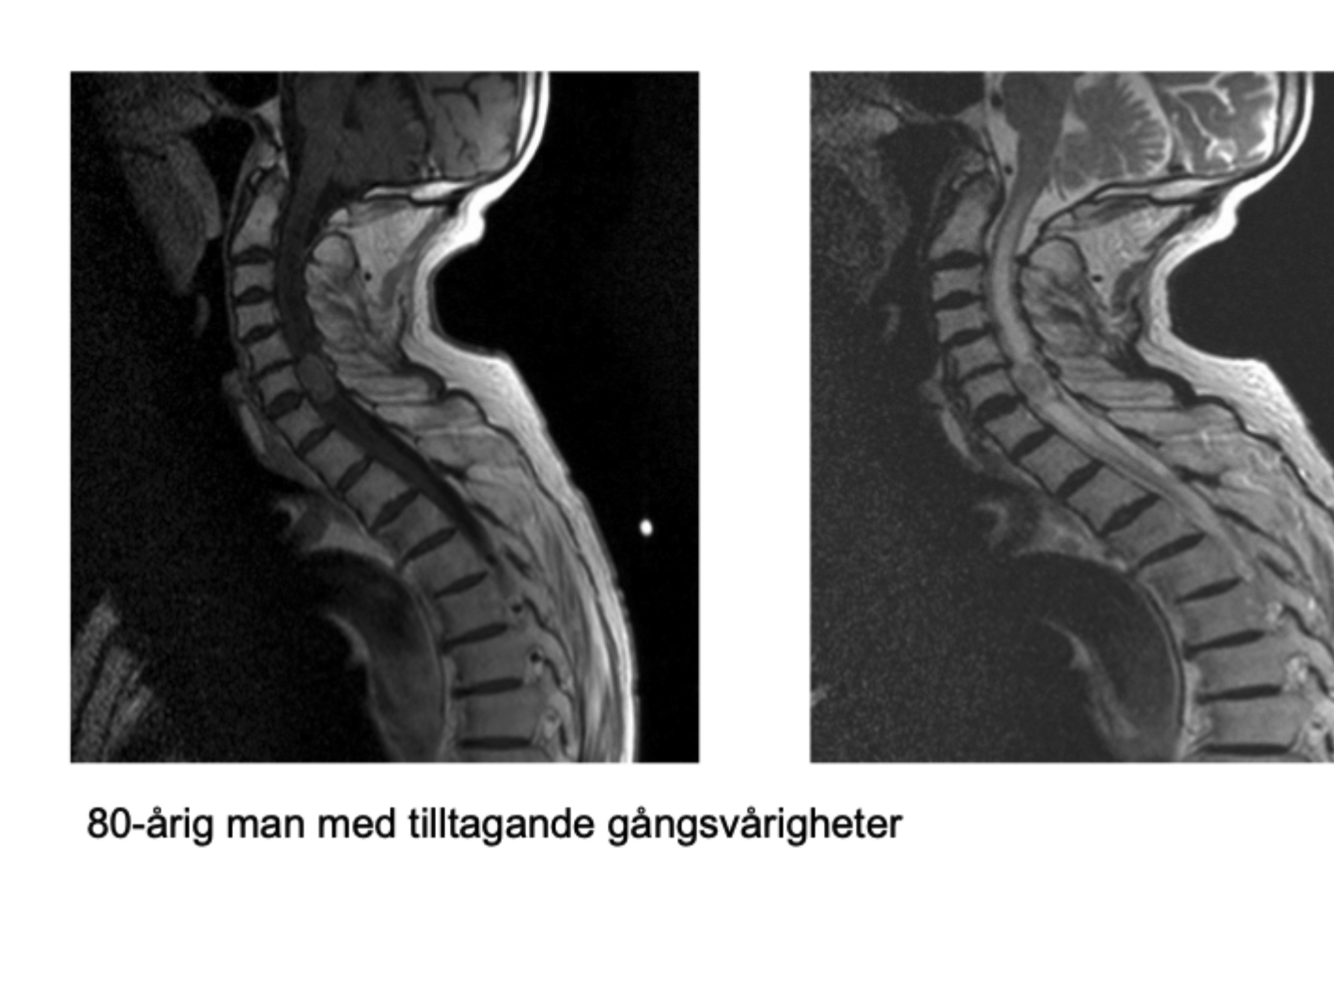

Q

Vad är detta? Kvinna med autoimmun sjukdom.